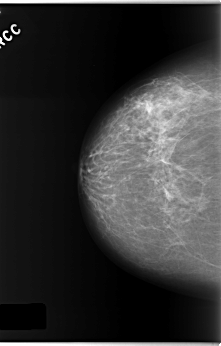

ics_version 1.0 filename C-0173-1 DATE_OF_STUDY 8 7 1996 PATIENT_AGE 67 FILM FILM_TYPE REGULAR DENSITY 2 DATE_DIGITIZED 12 3 1998 DIGITIZER LUMISYS LASER SEQUENCE LEFT_CC LINES 5936 PIXELS_PER_LINE 3688 BITS_PER_PIXEL 12 RESOLUTION 50 OVERLAY LEFT_MLO LINES 5880 PIXELS_PER_LINE 3552 BITS_PER_PIXEL 12 RESOLUTION 50 OVERLAY RIGHT_CC LINES 5872 PIXELS_PER_LINE 3752 BITS_PER_PIXEL 12 RESOLUTION 50 NON_OVERLAY RIGHT_MLO LINES 5896 PIXELS_PER_LINE 3808 BITS_PER_PIXEL 12 RESOLUTION 50 NON_OVERLAY |